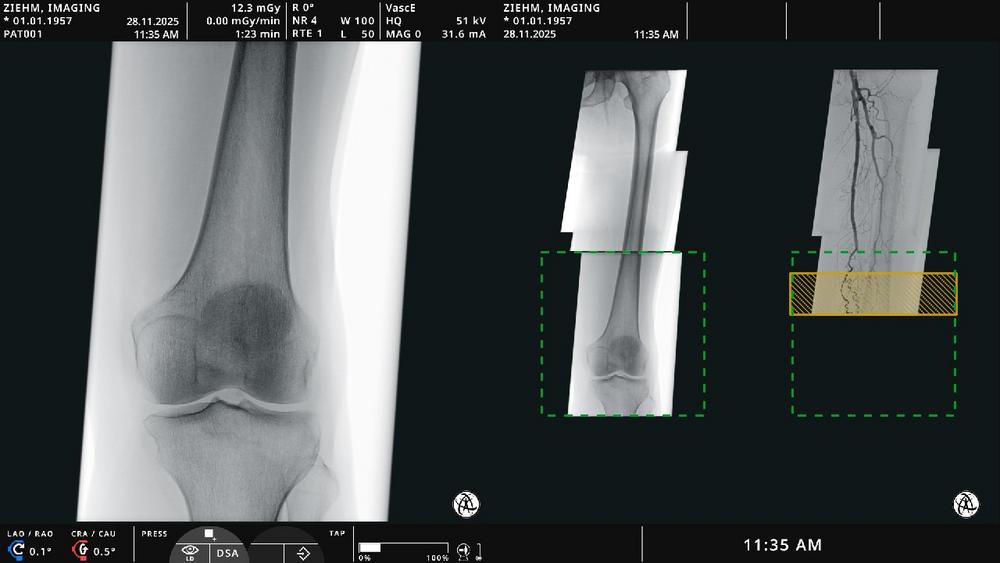

Endovascular Navigation Peripheral allows for panorama creation for peripheral artery disease cases by stitching fluoroscopic and angiographic images into a complete, up-to-date overview. Thrombotic and stenotic areas can be easily identified and marked. “Live fluoroscopic images align precisely with the angiographic panorama through image fusion—allowing clinicians to navigate with ease and optimal orientation without additional contrast media,” says Martin Törnvik, Vice President Global Sales & Marketing. Artificial intelligence-based algorithms automatically match and display image fusion – adapting in real time to patient, table, or C-arm movement. The solution is fully integrated into Ziehm Vision RFD Hybrid Edition3 (Cardio) and Ziehm Vision RFD 3D.